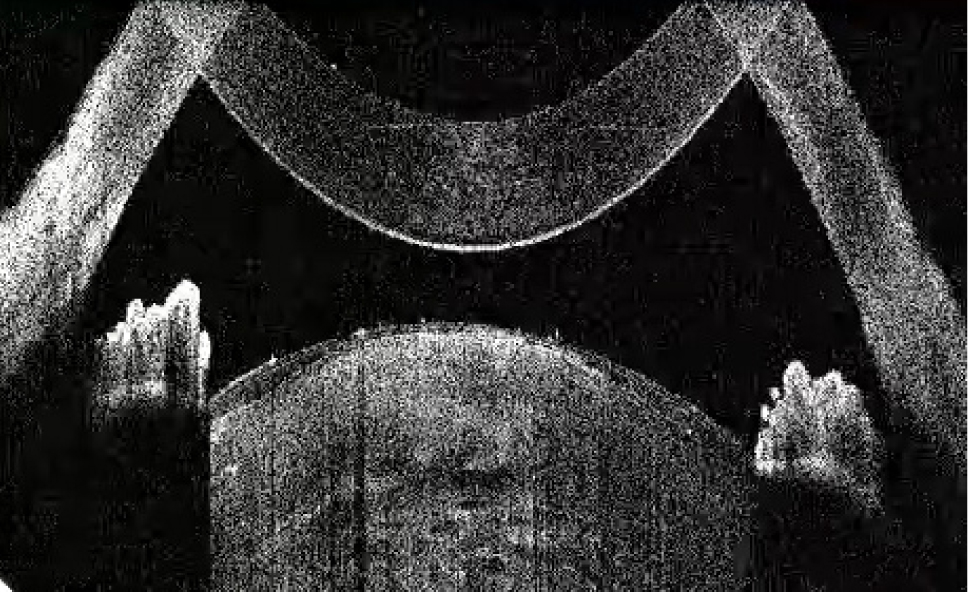

Рис. 1. Тип 1 перезрелой катаракты: равномерно расположенные кортикальные волокна, минимальные внутрихрусталиковые щели, отсутствие оводнения кортикальных масс

Рис. 2. Тип 2 перезрелой катаракты: непрерывные гиперрефлективные полосы кортикальных волокон, множественные внутрихрусталиковые щели, оводнение хрусталика